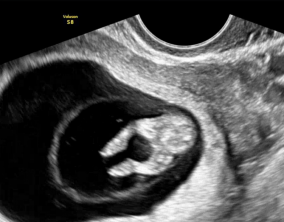

기대하지 않았던 두 줄, 그리고 끝까지 이어진 믿음